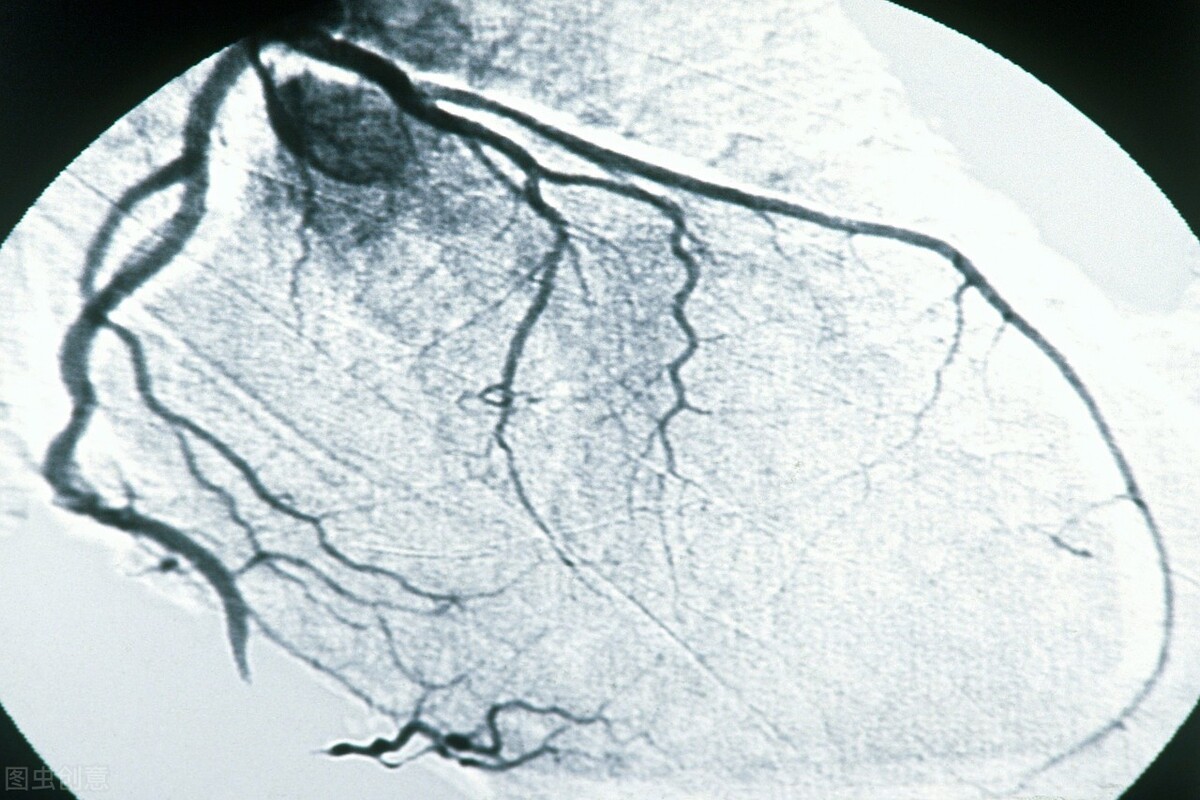

4冠脉造影 缺血性心脏病的“金标准”

冠脉造影属于有创性检查, 给身体造成的负担较冠脉CT大,但是准确性高,是诊断缺血性心脏病,例如冠心病、心梗的“金标准”。